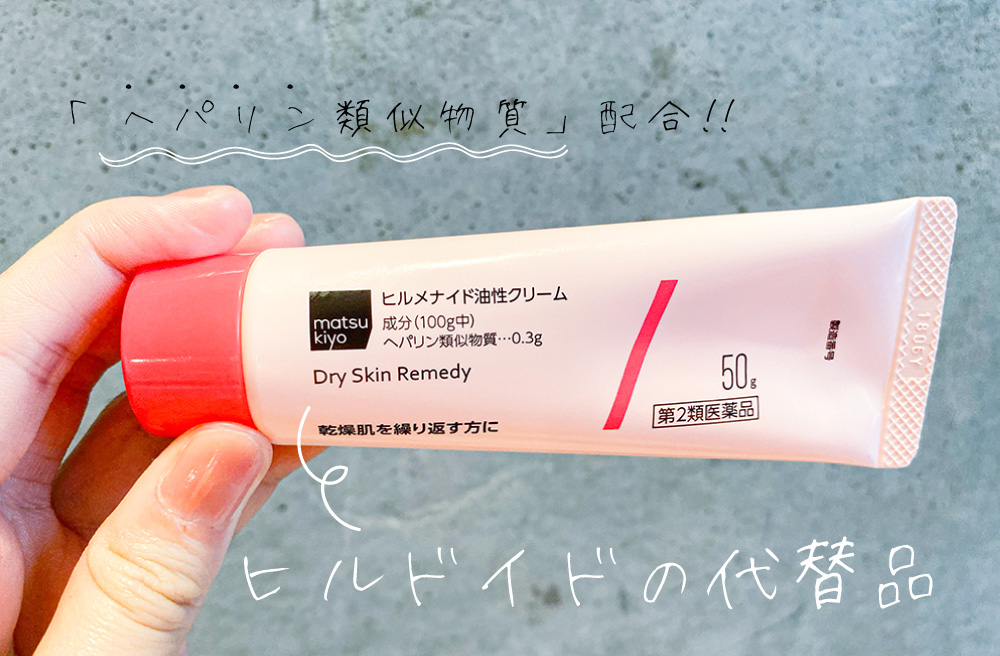

ヒルドイド って聞いたことありますか?

非常に優れた保湿効果のある「ヘパリン類似物質」を配合した最強保湿クリームと言われているものです☺︎

その実力はどんな高級保湿クリームもこれに勝てるものはないと言われているほど…!

ですが、ヒルドイドは病院の処方がないと手に入らない治療用なので、当たり前ですが美容目的の使用はNG!

そこでこの問題を解決すべく、

本家とほぼ同じ成分を店頭で購入できるようになったのが「ヒルメナイド」なんです♡

↑とってもプチプラ!マツキヨで売ってます♡

ヒルメナイド(1280円)を一緒揃えてもたった3,276円です!